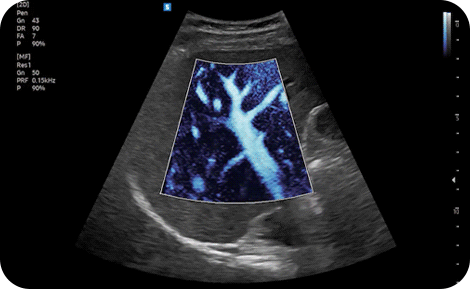

Show blood flow in vessels

in a 3D like display

LumiFlow™ ¹ is a function that visualizes blood flow in 3 dimensional-like to help understand the structure of blood flow and small vessels intuitively.

Examine peripheral vessels with

directional power Doppler

S-Flow™, a directional Power Doppler imaging technology, can help to detect even the peripheral blood vessels. It enables accurate diagnosis when the blood flow examination is especially difficult.